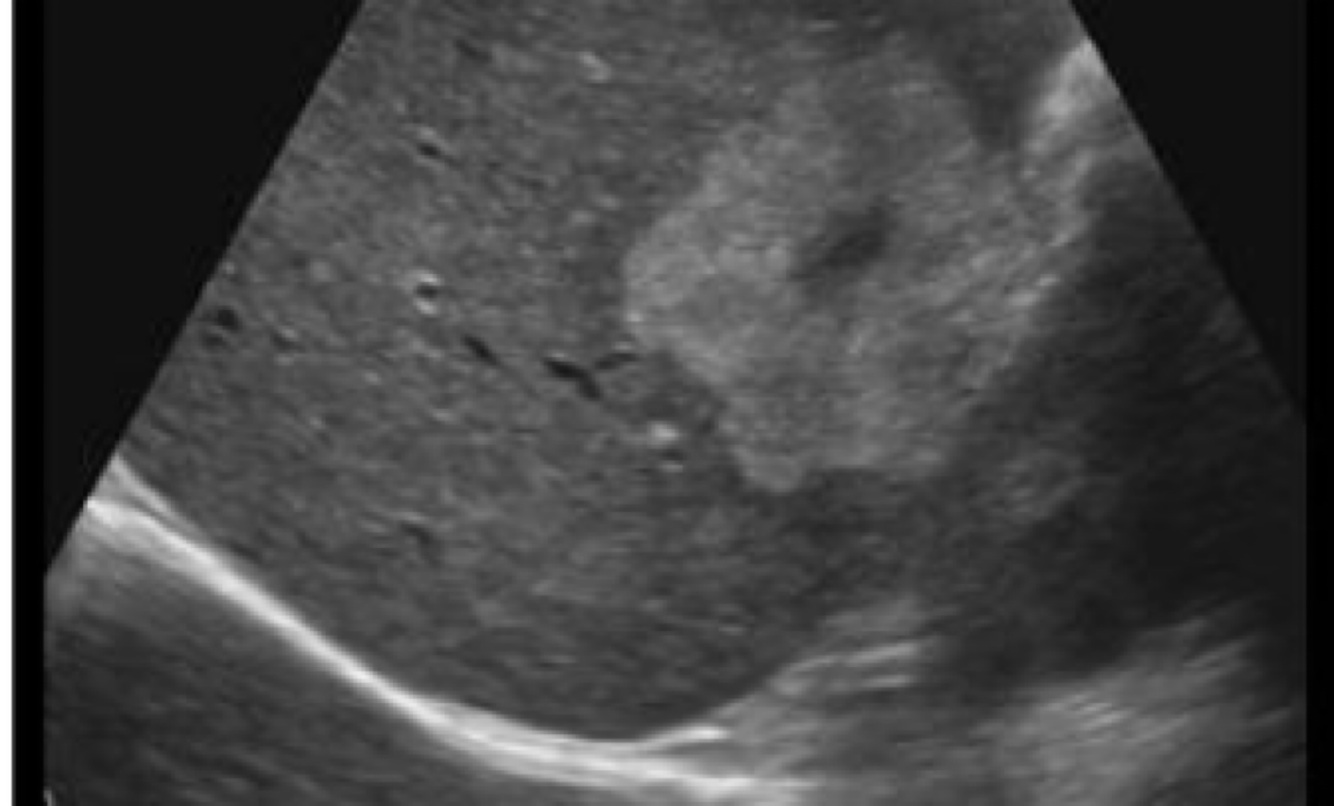

What does this image demonstrate?

Compression of adjacent organs